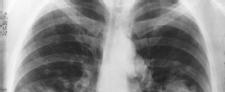

Medicare plans to start paying for lung cancer screening for people at high risk, a move that advocates say could save thousands of lives every year by catching the disease earlier.

The Centers for Medicare & Medicaid Services (CMS) made a formal proposal Monday to start paying for low-dose CT scans to look for lung tumors for people with a high risk of the world's No. 1 cancer killer.